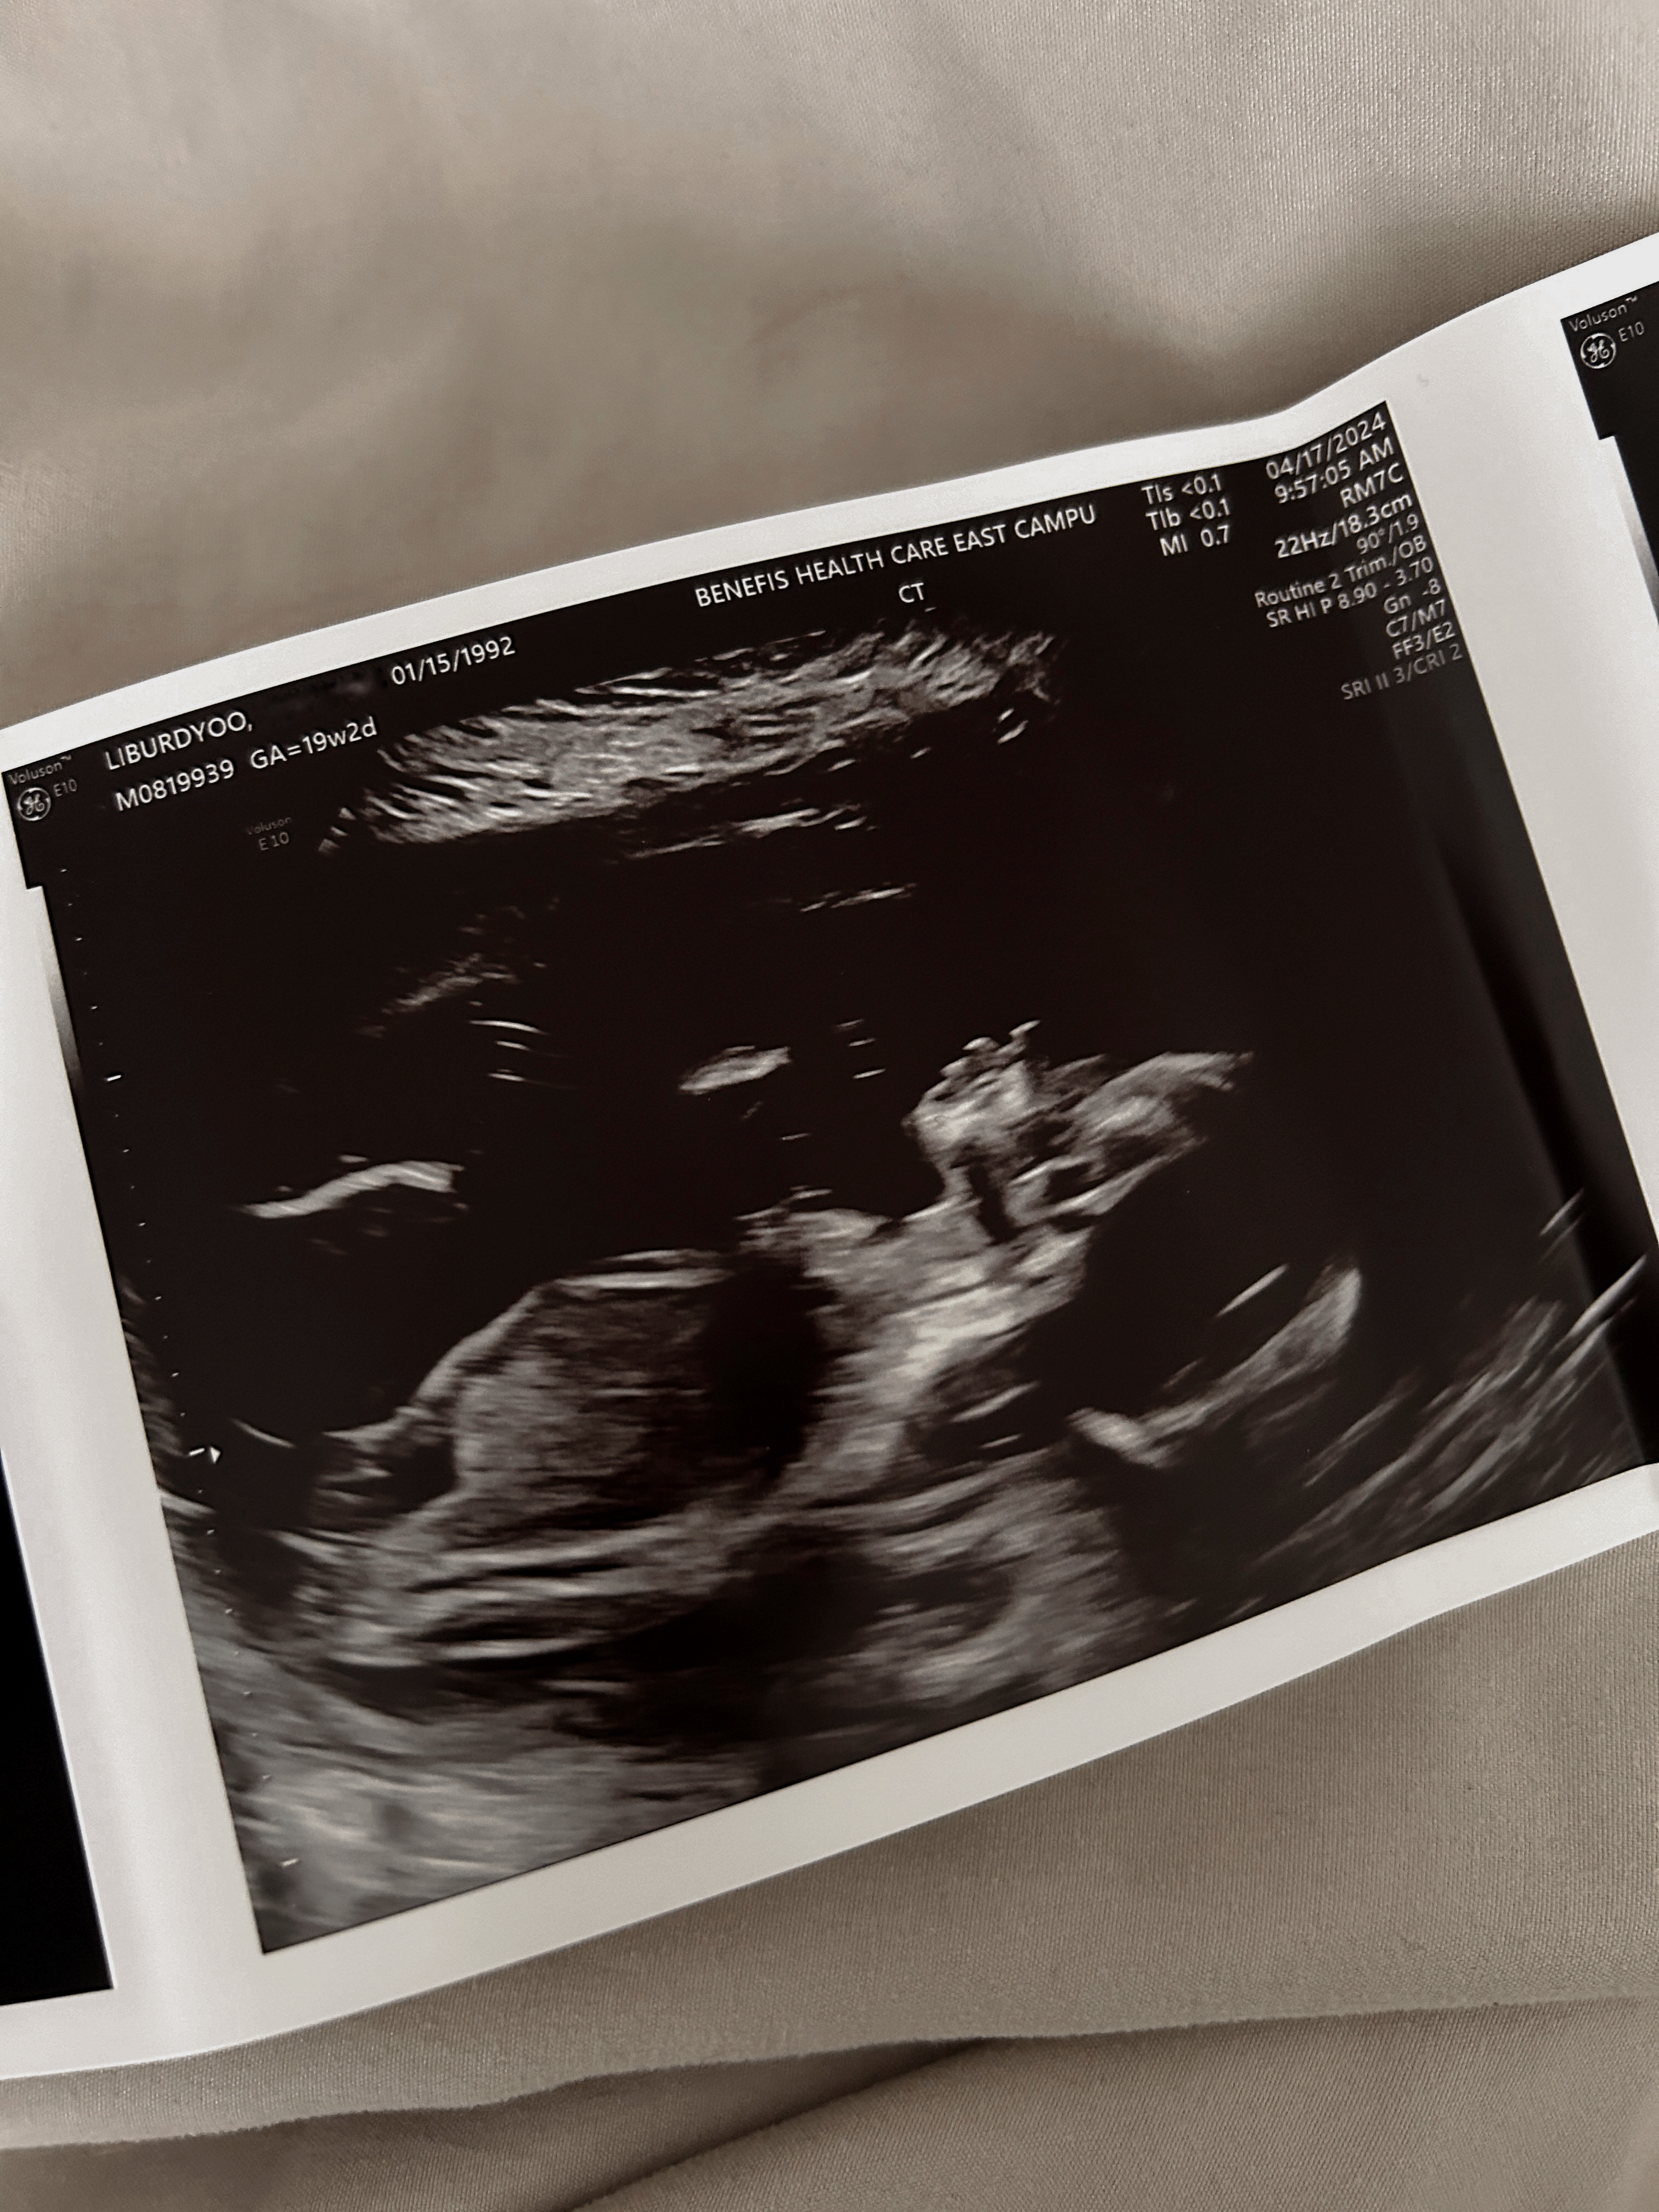

We had our anatomy scan around 19 weeks and 2 days. Crazy to think that we were able to see how much bigger our baby had grown since our 7 week scan. Now I can feel our baby moving around and even kicking me. In Korean culture is custom to nickname your baby and we decided on the nickname baby Channie since at the time we didn't know the gender BUT now we know!

So, I am proud to say that baby Channie is a GIRL! I cannot believe that I am going to be a girl mum.